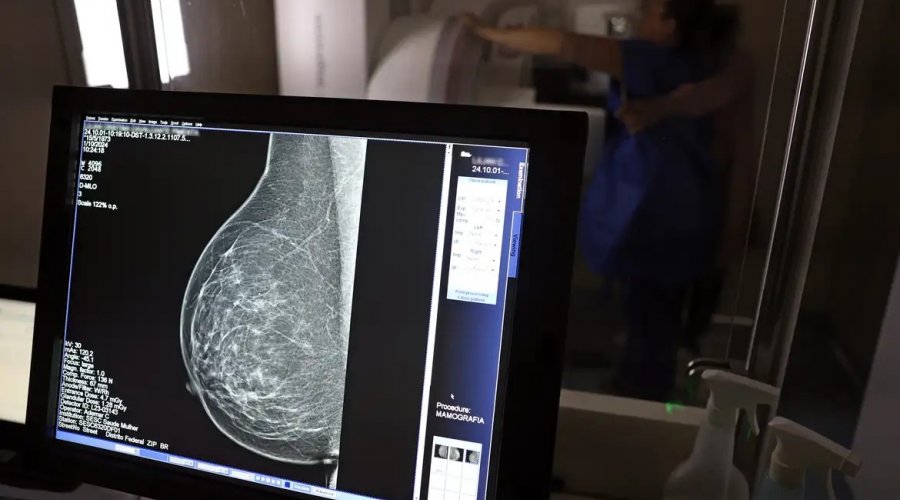

Foto: José Cruz/Agência Brasil

No Outubro Rosa, o Instituto Nacional de Câncer (Inca) estimou 73.610 novos casos este ano no país. É o câncer que mais mata mulheres no Brasil. As mulheres em tratamento pela doença têm o direito de receber o auxílio-doença ou o benefício de prestação continuada.